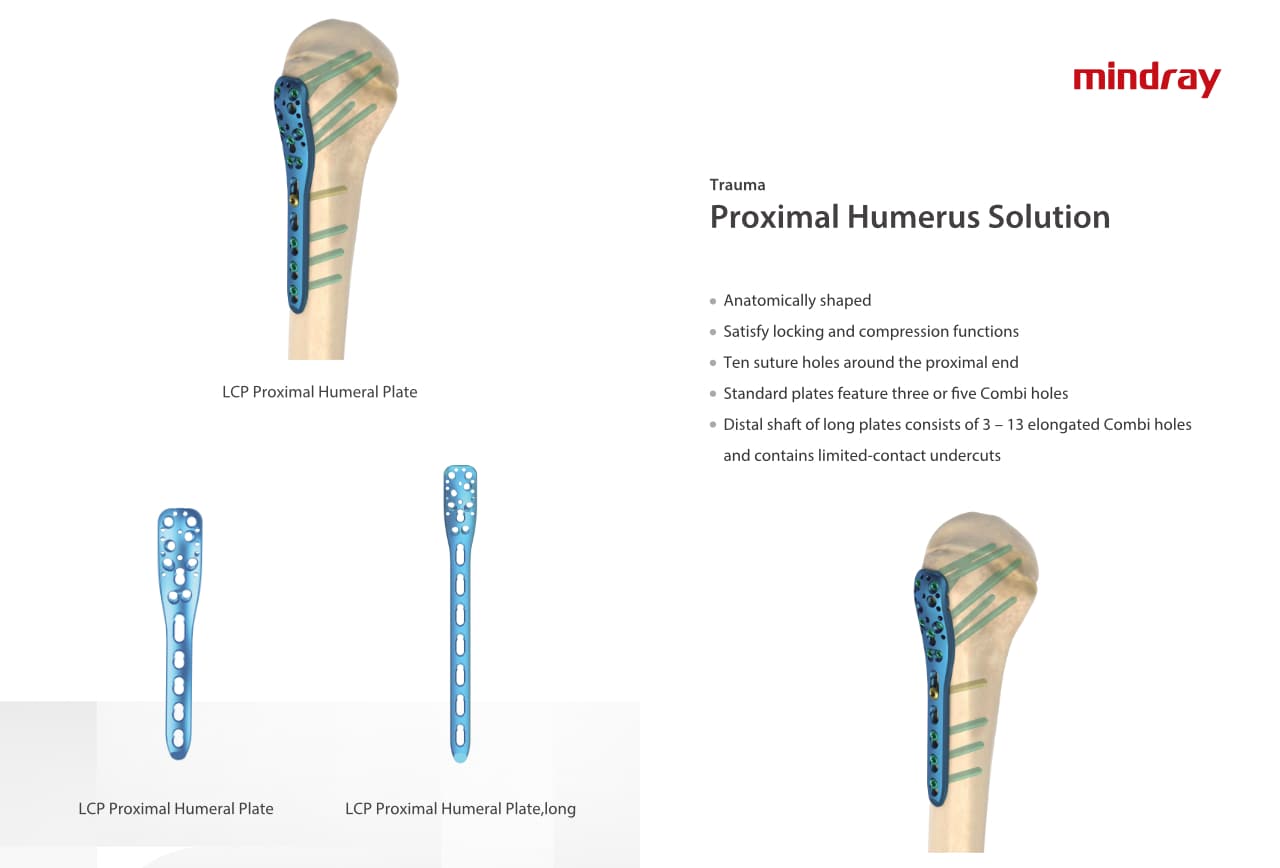

РһСҖСӮРҫРҝРөРҙРёСҮРөСҒРәРҫРө РҝРҫРҙСҖазРҙРөР»РөРҪРёРө РәРҫРјРҝР°РҪРёРё Mindray, СҖР°СҒРҝРҫР»РҫР¶РөРҪРҪРҫРө РІ РЈС…Р°РҪРө, СҸРІР»СҸРөСӮСҒСҸ РҫРҙРҪРёРј РёР· РІРөРҙСғСүРёС… РҝСҖРҫРёР·РІРҫРҙРёСӮРөР»РөР№ РҫСҖСӮРҫРҝРөРҙРёСҮРөСҒРәРҫР№ РҝСҖРҫРҙСғРәСҶРёРё РёР· РҡРёСӮР°СҸ. РһРҪРҫ Р·Р°РҪРёРјР°РөСӮСҒСҸ РёСҒСҒР»РөРҙРҫРІР°РҪРёСҸРјРё Рё СҖазСҖР°РұРҫСӮРәРҫР№, РҝСҖРҫРёР·РІРҫРҙСҒСӮРІРҫРј Рё РјР°СҖРәРөСӮРёРҪРіРҫРј СӮСҖавмаСӮРҫР»РҫРіРёСҮРөСҒРәРёС… Рё СҒРҝРёРҪалСҢРҪСӢС… РёР·РҙРөлий, РҝСҖРҫРҙСғРәСҶРёРё РҙР»СҸ Р°СҖСӮСҖРҫРҝлаСҒСӮРёРәРё Рё РҙСҖСғРіРёС… С…РёСҖСғСҖРіРёСҮРөСҒРәРёС… РёР·РҙРөлий. РЎ РјРҫРјРөРҪСӮР° СҒРІРҫРөРіРҫ РҫСҒРҪРҫРІР°РҪРёСҸ РІ 1999 РіРҫРҙСғ РјСӢ СғСҒРҝРөСҲРҪРҫ РҝСҖРҫСҲли СҒРөСҖСӮифиРәР°СҶРёСҺ ISO 9001, ISO 13485 Рё CE, РІСӢРҙР°РҪРҪСғСҺ T?V Рё СҚРәСҒРҝРҫСҖСӮРёСҖСғРөРј РҝСҖРҫРҙСғРәСҶРёСҺ РІ РұРҫР»РөРө СҮРөРј 50 СҒСӮСҖР°РҪ РҝРҫ РІСҒРөРјСғ РјРёСҖСғ.